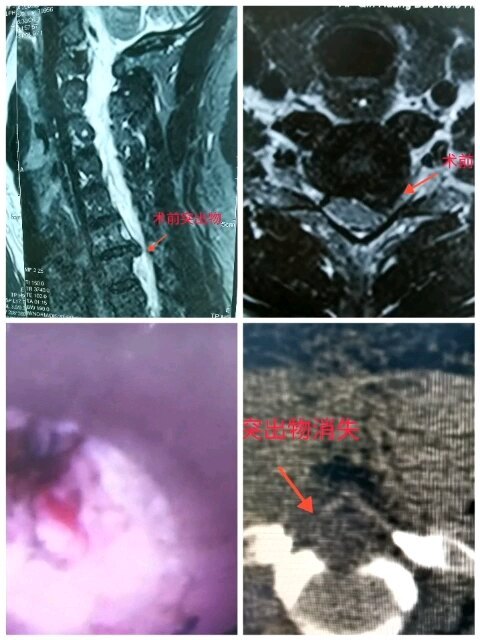

治療前嚴(yán)重的頸椎后縱韌帶骨化導(dǎo)致脊髓型頸椎病,上肢疼痛、麻木、無(wú)力上舉活動(dòng)受限,局部肌肉萎縮伴下肢踏棉感。治療中完善相關(guān)化驗(yàn)檢查,全麻下行后入路脊柱內(nèi)鏡下椎板切除術(shù)治療后治療后100天雙上肢疼痛消失,麻木明顯改善,肌力恢復(fù)正常,下肢踏棉感消失。

耿海濤? 主治醫(yī)師? 秦皇島市第三醫(yī)院? 疼痛科135人已讀 - 精選 脊柱內(nèi)鏡微創(chuàng)手術(shù)取出頸椎間盤突出物(神經(jīng)根型)蘇啟超? 主任醫(yī)師? 秦皇島市第三醫(yī)院? 疼痛科753人已觀看